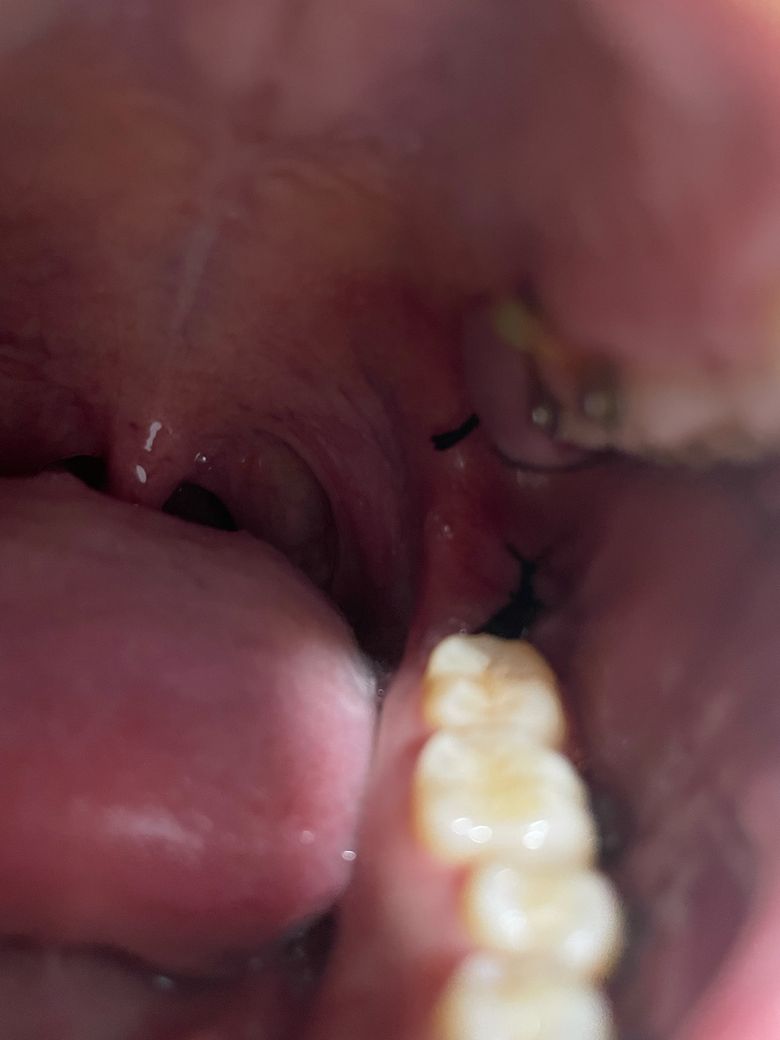

사랑니 발취 후 염증? 도와주세요ㅜㅜ

사랑니 뽑고 위쪽에 저렇게 하얗게 부어올랐는데 저게 염증인가요? 집에서 해결되나요? ㅜㅜ 도와주세요

시간 지나면 해결되는건가요?

발치 후 얼마나 지났을지 모르겠으나 일단 치과를 가보시고 적절한 조치, 약처방 받으시기 바랍니다.